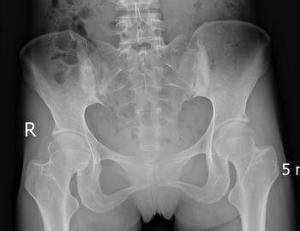

体格检查:脊柱生理弯曲度消失,颈部活动受限,前仰30°,后仰15°;腰椎活动受限,前屈70°,后屈0°;右髋关节压痛(+),右膝呈伸–4度畸形,左膝屈90度,伸–10度;骨盆挤压分离试验(+),双"4"字测试查体欠合作;枕墙距16cm,胸廓扩张度1.0cm。

辅助检查:CPR:33.08mg/l,RF:12.30Iu/ml,ESR:55.0mm/h;HLA-B27(+)X光片示:椎体向右侧弯曲,间隙模糊狭窄,骶髂关节炎。

(图:患者骶髂关节X线片)